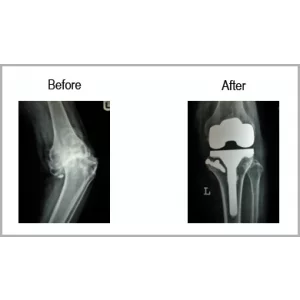

Osteoarthritis With Large Bony Defect

A female aged 72 years has knee pain for more than 15 years. She had osteoarthritis with significant bone loss. She was hardly able to walk and that to with support only. She had more than just “Bow legs”.

She had both knee replacement using bone graft with long stem. Her legs become straight as normal and she is back on her toes. She is able to walk independently and without any support.